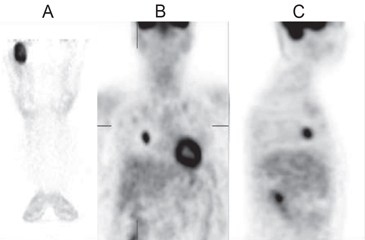

Se realizó una PET que evidenció un tumor en el muslo derecho e imágenes pulmonares compatibles con metástasis (Figura 1). La biopsia del muslo mostró un tumor que infiltraba la musculatura estriada y el tejido óseo, correspondiente a sarcoma fusocelular G2 concordante con fibrosarcoma (Figura 2). Se tomó muestra venosa periférica en antebrazo derecho para medición de FGF-23 por método ELISA, que resultó muy elevado, > 5.000 unidades de referencia (RU)/mL, (VN < 150 RU/mL). Se procedió a amputar la extremidad inferior derecha y se planificó la resección de la metástasis; sin embargo, al momento de la intervención se encontraron múltiples metástasis pulmonares inabordables, por lo cual la paciente fue dada de alta con tratamiento paliativo, recibiendo bifosfato de sodio, calcio y 1,25 dihidroxi-D3. Pasado un año desde el alta se encontraba en condiciones similares a las de su egreso.

Figura 1. PET-FDG: Se aprecia marcado aumento de la captación del trazador en la lesión del muslo proximal derecho (corte coronal, A) y en metástasis pulmonar derecha (corte coronal, B, en el que se ve también actividad fisiológica de corazón, y corte sagital, C).